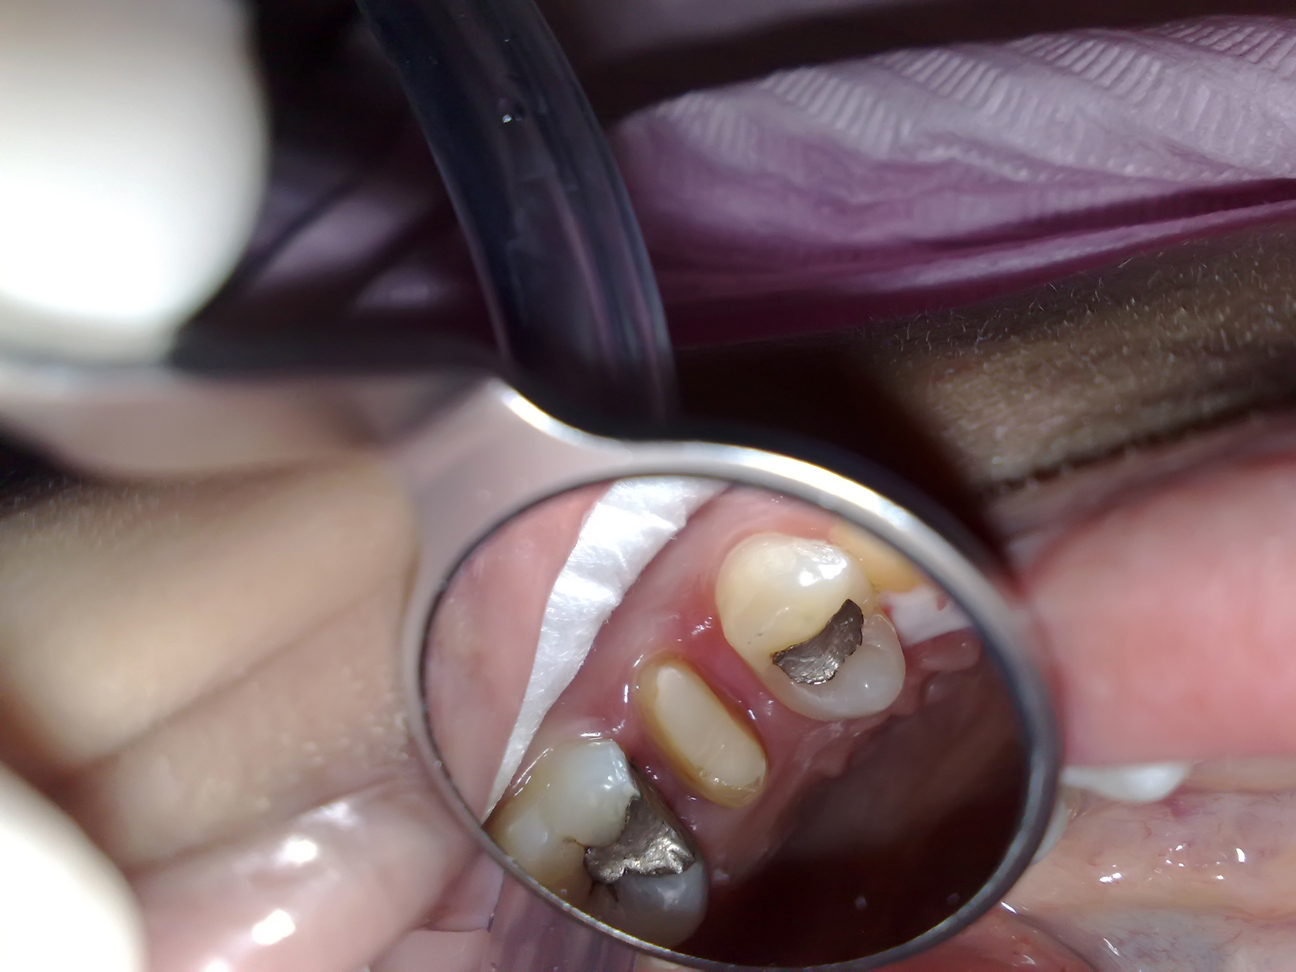

Endodontic treatment on upper left first molar with broken mesial and distal wall